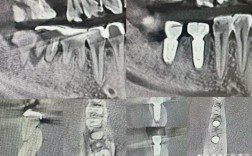

- 检查前准备:携带口腔CT片供放射科参考,明确种植体位置与检查部位的空间关系。